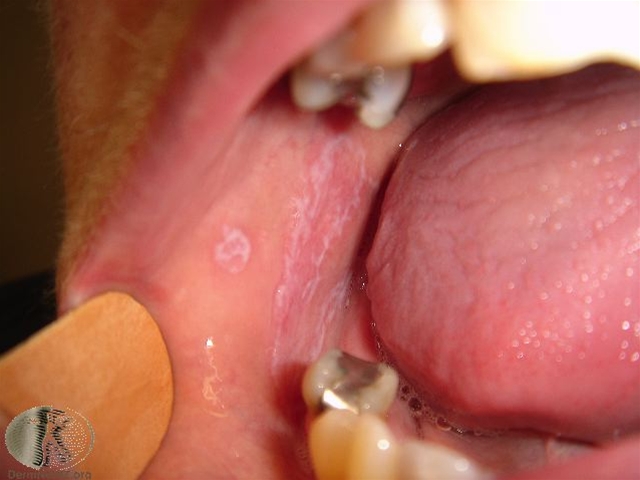

Lichen planus på slimhinde.